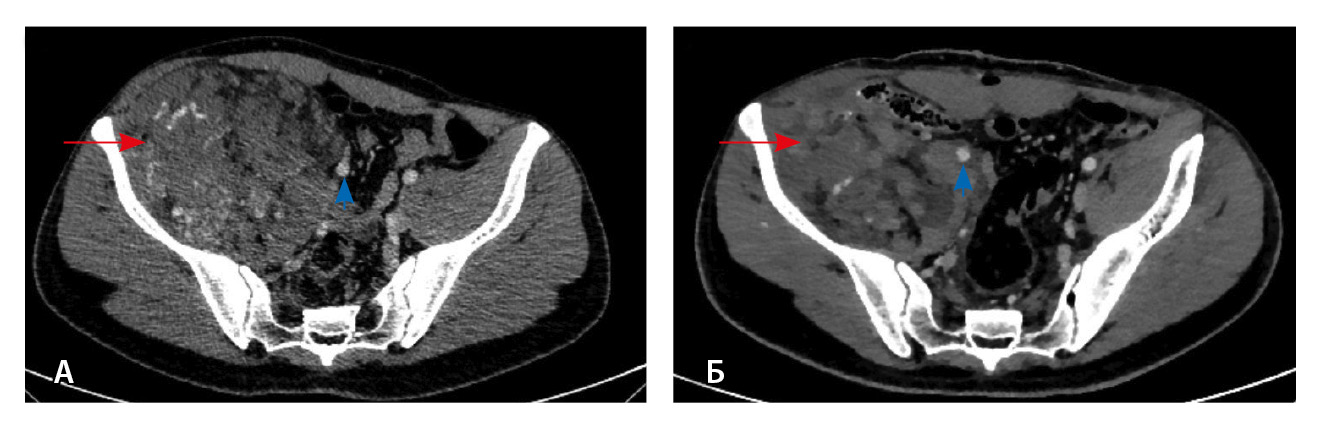

Результаты дооперационной мультиспиральной компьютерной томографии органов брюшной полости и забрюшинного пространства (рис. 1, 2): «В забрюшинном пространстве справа визуализируется образование, исходящее из подвздошно-поясничной мышцы, с выходом вдоль сосудистого пучка на верхнюю треть бедра. Образование с четкими и ровными контурами, размерами 145 × 125 × 125 мм. Структура образования гетерогенная, плотность в нативную фазу исследования от –40 до 50 HU, содержит единичные кальцинаты, жировую ткань и мягкотканный компонент. На фоне контрастирования в артериальную и венозную фазы в структуре выявляются извитой формы участки гиперконтрастирования (сосудистая сеть). Максимальное накопление контрастного препарата происходит преимущественно к отсроченной фазе исследования. Усредненные плотностные характеристики составляют 25, 36, 53 и 59 HU в нативную, артериальную, венозную и отсроченную фазы соответственно. Опухоль оттесняет тазовую брюшину, правую подвздошно-поясничную мышцу, илеоцекальный угол кпереди. Образование тесно прилежит сзади к крылу правой подвздошной кости и лобковой кости, спереди – к прямой и внутренней косым мышцам живота, верхним контуром – к поясничной мышце. Медиально в средней трети по контуру образования проходят правые наружные и внутренние подвздошные сосуды, со сдавлением наружной подвздошной вены. Данных за распространение на прилежащие внутренние органы и клетчатку не получено. Кости без деструктивных изменений».

Рис. 1. Мультиспиральная компьютерная томография органов брюшной полости и забрюшинного пространства с болюсным внутривенным контрастированием: А – нативная фаза, Б – артериальная фаза, В – венозная фаза, Г – отсроченная фаза. Крупное гетерогенной структуры образование забрюшинного пространства справа, с фокусами гиперваскуляризации в структуре. Тесно прилежит к крылу подвздошной кости и подвздошным сосудам, оттесняя последние медиально